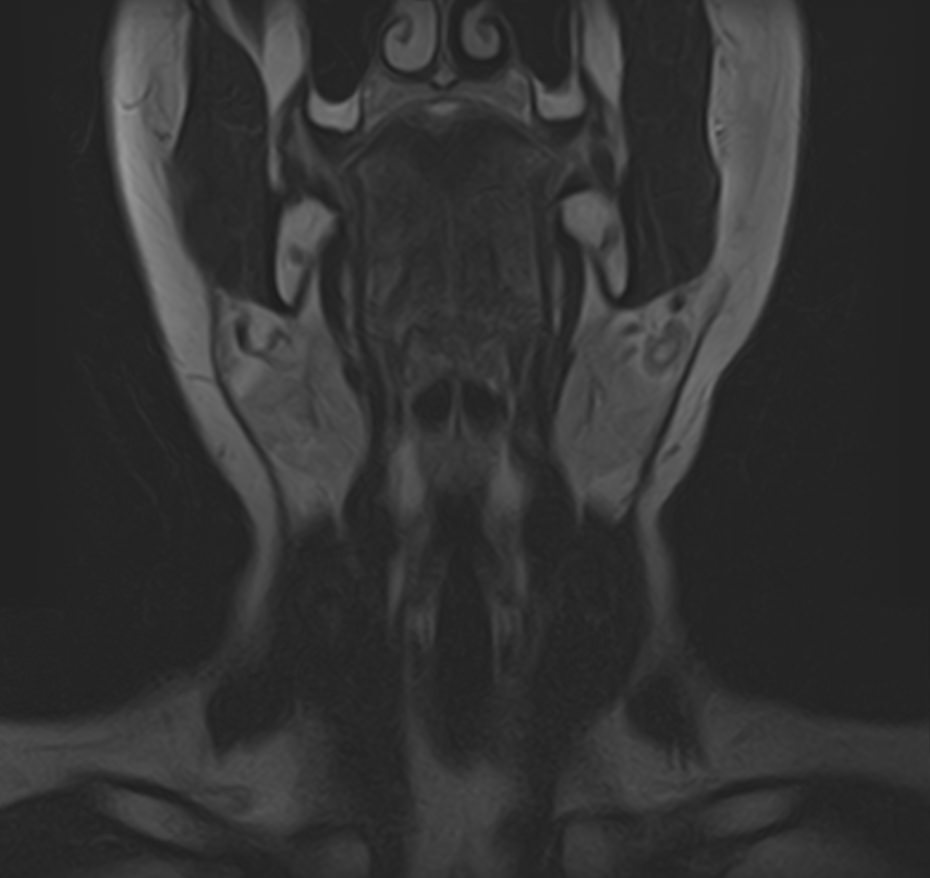

Магнитно-резонансная томография шеи предусматривает детальную визуализацию различных анатомических структур области шеи. Сюда входит полость рта, язык и корень языка, пищевод, гортань, окологлоточные лимфоузлы, шейные лимфоузлы, слюнные железы, щитовидная железа, мышцы и межфасциальные пространства.

В нашей клинике данное обследование выполняется на новейшем 32-канальном высокопольном томографе закрытого типа TOSHIBA VANTAGE TITAN 1,5 Тесла. Высокотехнологичный аппарат производит сканирование путем тончайших срезов с шагом от 1 мм в трех различных плоскостях. Используя современные компьютерные программы, полученные данные преобразуются в 3D-изображение исследуемой зоны. Это обеспечивает точность и достоверность диагностики заболеваний анатомических структур, расположенных в области шеи.